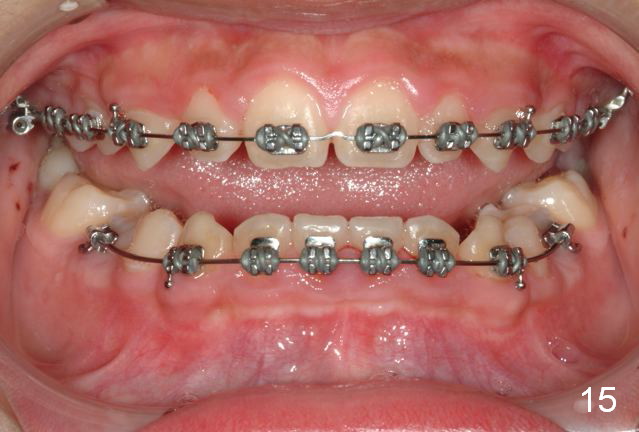

Brackets were placed on 2015_09_06 (Fig.11-13, Phase I pre-orthopedic tooth movement, leveling in advance of Herbst appliance therapy using ankylosed Es).   Six months later (Fig.14-16), LR7 did better, LL7 did not and will need intervention. But intrusion of L 3-3 looks good.

Dear Dr. Shaughness: It is good thinking and result. But if bands were placed on L6s, the result may have been be the same?  How old is the boy?   Why not place brackets on L4?  Can we slenderize LL E to make space for LL7 eruption?   Thanks.

Now back to orthodontics, I did not want to place bands on the lower 6s initially because I thought that would block the ectopic 7s for sure and seal their fate.

The effect would be quite similar had I banded the 6s but we know they can move, the Es cannot.

I will have the LL8 extracted and the adjacent 7 elevated and/or place an interdental brass wire. I will have it up righted in no time and not plan to slenderize the E.